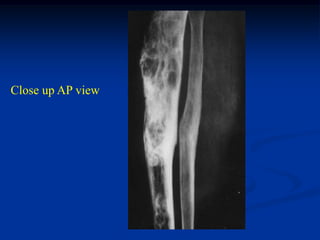

Case #217

25 year female

adamantinoma tibia

Close up AP view